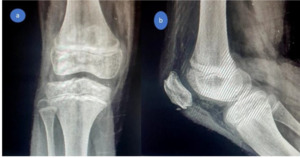

By three to four months, both patients had achieved full knee ROM, restoration of quadriceps strength, and radiographic evidence of complete fragment healing (Figures 9, 10). Return to normal daily activity occurred between the third and fourth months, with clearance for sports and play at six months.

At final follow-up—12 months for Case 1 and 18 months for Case 2—both children were asymptomatic, with full ROM, normal quadriceps power, and no growth-related complications. Radiographs confirmed a well-centered patella with complete bony healing (Figures 11, 12).